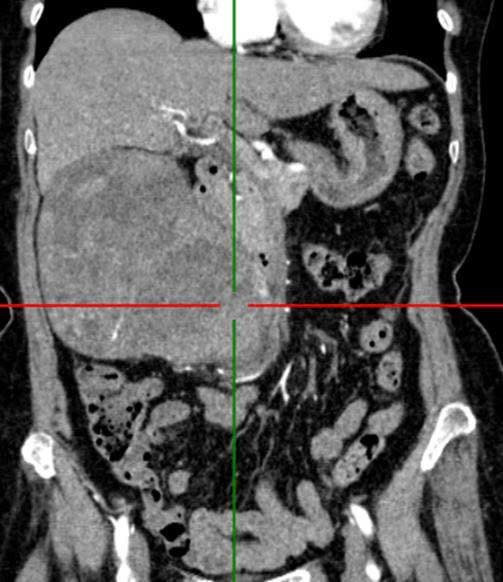

Khối u thận kích thước lớn trên phim chụp - Ảnh BVCC

Cận lâm sàng: Cắt lớp vi tính bụng (1-32 dãy có thuốc): Thận phải: To, nhu mô không đều, có hình ảnh khối choán chỗ ngấm thuốc mạnh sau tiêm, KT (118 x 133 x 135)mm. Đài bể thận giãn, không thấy sỏi. Kết luận u thận phải.